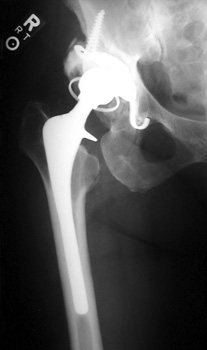

Broken femoral stem with remodeling of the lateral femoral cortex.